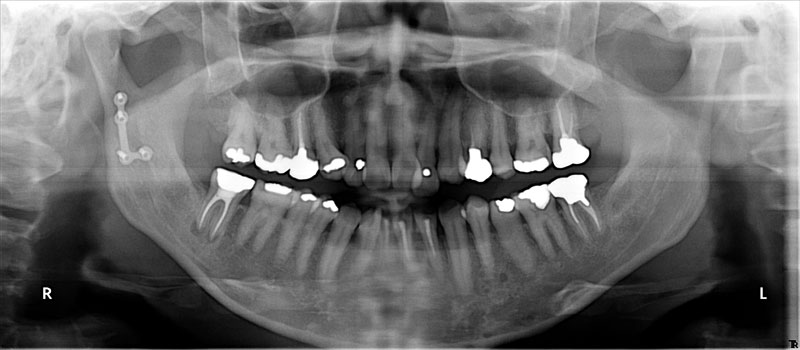

術前

- 初診:2006年。2010年―矯正治療を含めた一口腔単位の治療開始、治療当時、30代女性、喫煙者

- 矯正診断:3級骨格性の反対咬合

- 治療方針:以前に治療した歯の再治療(虫歯治療、歯内療法、歯周処置)、右下前歯1本抜歯、矯正用インプラントを用いたワイヤー矯正、修復処置(被せ物)、保定(上ワイヤー、下マウスピース)、歯茎のピーリング(漂白)、4か月メンテナンス